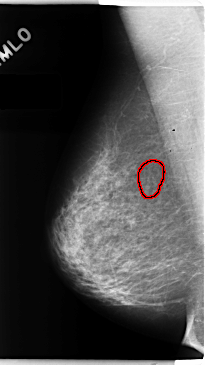

C_0151_1.RIGHT_MLO

RIGHT_MLO LINES 4736 PIXELS_PER_LINE 2656 BITS_PER_PIXEL 12 RESOLUTION 50 OVERLAY

FILE: C_0151_1.RIGHT_MLO.OVERLAY

TOTAL_ABNORMALITIES 1

ABNORMALITY 1

LESION_TYPE CALCIFICATION TYPE PLEOMORPHIC DISTRIBUTION CLUSTERED

ASSESSMENT 4

SUBTLETY 3

PATHOLOGY MALIGNANT

TOTAL_OUTLINES 1